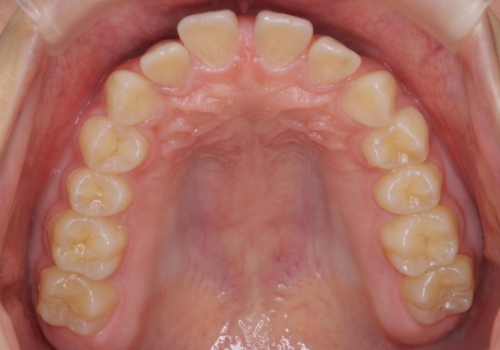

- 10代女性

- ワイヤー矯正

- 前歯のすき間を気にして来院。

全体矯正ではなく部分矯正で治療することになりました。

その代わり、すき間をすべて閉じるのは難しく、両脇の目立たないところに集めて治療終了しています。